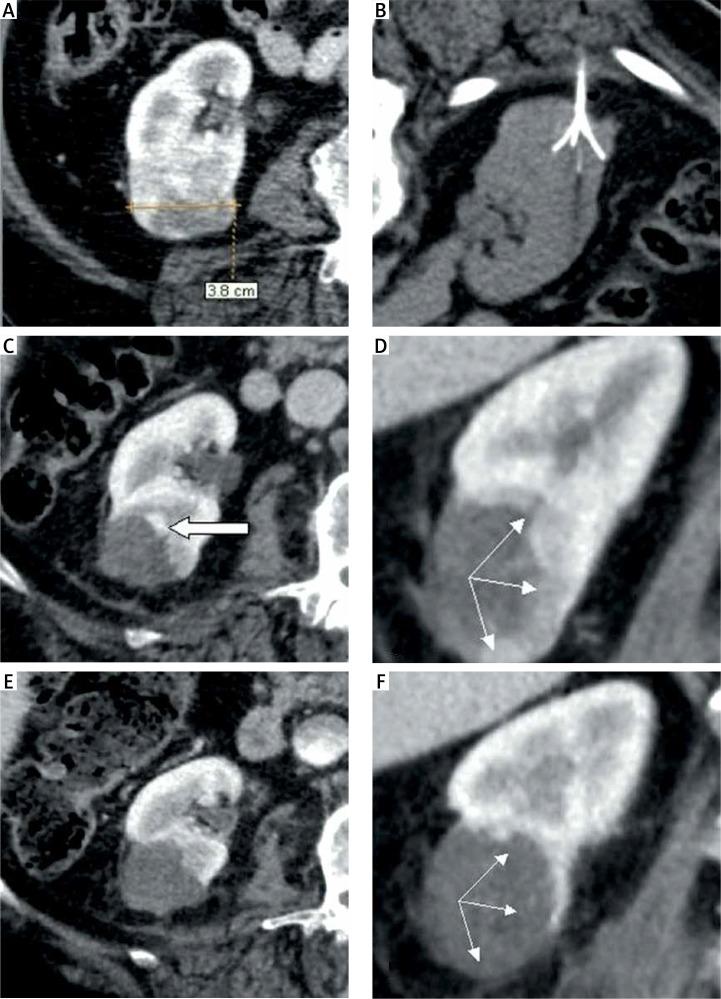

Over the course of 10 years, 91 ablation procedures in 64 patients for 68 tumors, of size 12-60 mm, were performed using only conscious sedation. These ablations were done under the guidance of computed tomography. We treated 41 males and 23 females with solitary kidney tumors (14 cases) and tumors in non-surgical candidates (54 cases).

In 50 (73.5%) tumors single treatment was successful; in 13 (19.1%) cases a second procedure was used successfully, and in the 5 largest tumors (sizes 45-60 mm, 7.4%) a third treatment was necessary. Within the follow-up 10 (15.6%) patients died, but none due to metastatic renal cell carcinoma. Only 1 serious complication was observed - retroperitoneal and psoatic hematoma. Early recurrence occurred in 18 (26.5%) tumors. Late recurrence was detected in 5 (7.4%) cases. In all cases complete local control of the renal tumors was reached.

在10年期间,对64例患者的68个大小为12 - 60毫米的肿瘤进行了91次消融手术,仅采用清醒镇静。这些消融手术在计算机断层扫描引导下进行。我们治疗了41例男性和23例女性,其中包括孤立肾肿瘤患者(14例)和不适合手术的肿瘤患者(54例)。

50个(73.5%)肿瘤单次治疗成功;13例(19.1%)患者成功进行了第二次手术,5个最大的肿瘤(大小为45 - 60毫米,占7.4%)需要进行第三次治疗。在随访期间,10例(15.6%)患者死亡,但均非死于转移性肾细胞癌。仅观察到1例严重并发症——腹膜后和腰大肌血肿。18个(26.5%)肿瘤发生早期复发。5例(7.4%)出现晚期复发。所有病例均实现了肾肿瘤的完全局部控制。